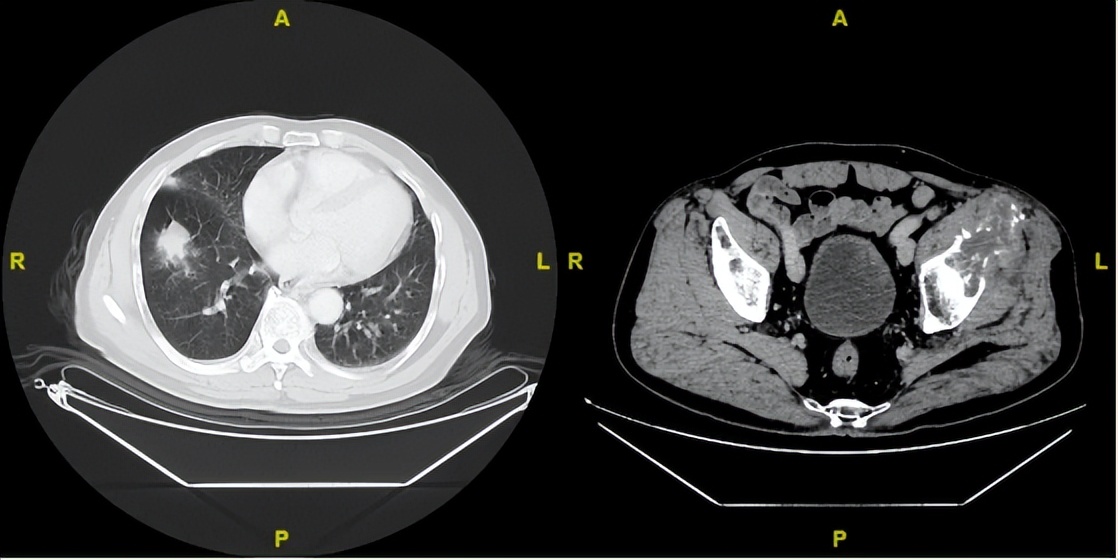

基线(2022年12月13日)

△基线胸部CT和盆腔CT髂骨病灶